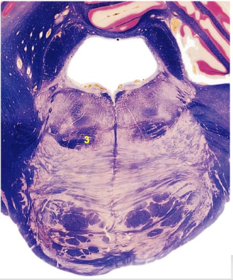

| Medullary pyramids | |

| Hypoglossal nucleus | |

| Hypoglossal nerve | |

| Dorsal motor nucleus of X | |

| Nucleus ambiguus | |

| Solitary tract | |

| Solitary nucleus | |

| ALS | |

| Medial lemniscus | |

| Medial longitudinal fasciculus | |

| Anterior spinocerebellar tract | |

| CN IX | |

| Inferior cerebellar peduncle | |

| Inferior olivary complex | |

| Dorsal cochlear nucleus | |

| Inferior vestibular nucleus | |

| Medial vestibular nucleus | |

| Spinal nucleus of V | |

| Spinal tract of V | |